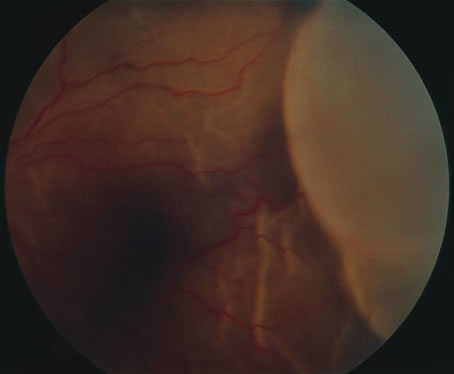

In primary ocular HSV infections, a severe follicular conjunctivitis with regional adenopathy is present. Vesicles may appear on the eyelid skin or lid margin, producing blepharitis (Fig. 3). Corneal involvement initially takes the form of a superficial punctate keratitis, which may progress to dendritic or geographic ulceration. Stromal infiltrates and uveitis are less common and relatively mild in primary disease. In uncomplicated cases, lesions usually heal completely in 2 to 3 weeks without scarring. Most cases of ocular HSV are recurrences. Recrudescent ocular herpes may take the form of dendritic or geographic ulcers, recurrent erosions, interstitial or disciform stromal keratitis, and anterior uveitis.3 HSV may also be an agent of retinitis and acute retinal necrosis (Fig. 4).

The acute retinal necrosis (ARN) syndrome is most often caused by the herpes zoster virus, although occasionally it may be a result of herpes simplex infection.12 It is typically described in healthy patients although association with immunosuppressed patients has also been described. Granular, nonhemorrhagic areas of retinal necrosis may be observed in the fundus, often rapidly coalescing with resulting blindness often caused by retinal detachment. There is often an associated vasculitis and vitritis. In immunocompromised patients VZV or HSV retinitis may also take the pattern of progressive outer retinal necrosis (PORN) (Fig. 6). PORN differs from ARN in that the former is multifocal, localized to the outer retina, and is less often associated with vasculitis and vitritis.